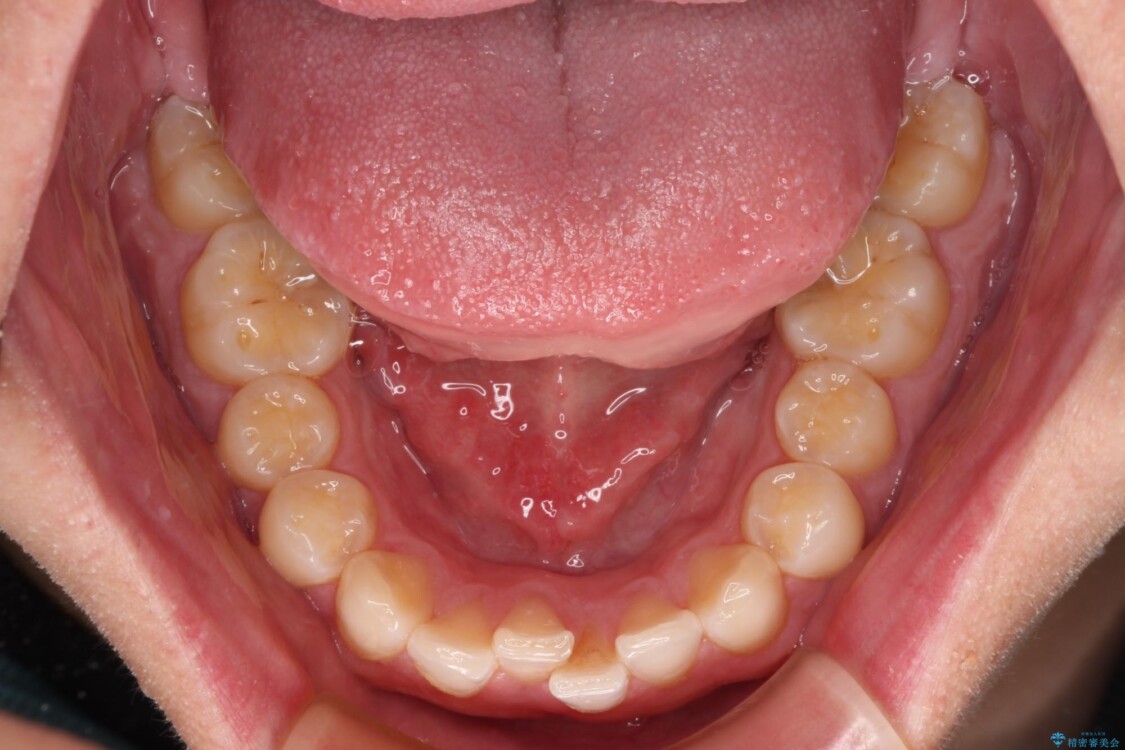

治療前

• 前歯のガタガタ・奥歯のかみ合わせ(シザーズバイト)を改善|1年半で完了したメタルブラケット矯正 治療前画像

・上顎左右の第二大臼歯が頬側へ転移し、シザーズバイト(scissors bite)の状態

・上顎左側第二小臼歯が90度捻転しており、噛み合わせに影響